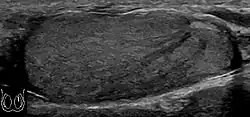

However, these patterns, except the latter one, may be considered as non-specific as heterogeneous echotexture and shadowing calcification can also be detected in malignant testicular tumors. The onion peel pattern of epidermoid cyst [Fig. 10] correlates well with the pathologic finding of multiple layers of keratin debris produced by the lining of the epidermoid cyst. This sonographic appearance should be considered characteristic of an epidermoid cyst and corresponds to the natural evolution of the cyst. Absence of vascular flow is another important feature that is helpful in differentiation of epidermoid cyst from other solid intratesticular lesions.

Epidermoid cysts, also known as keratocysts, are benign epithelial tumors which usually occur in the second to fourth decades and accounts for only 1–2% of all intratesticular tumors. As these tumors have a benign biological behavior and with no malignant potential, preoperative recognition of this tumor is important as this will lead to testicle preserving surgery (enucleation) rather than unnecessary orchiectomy. Clinically, epidermoid cyst cannot be differentiated from other testicular tumors, typically presenting as a non-tender, palpable, solitary intratesticular mass. Tumor markers such as serum beta-human chorionic gonadotropin and alpha-feto protein are negative. The ultrasound patterns of epidermoid cysts are variable and include:

- A mass with a target appearance, i.e. a central hypoechoic area surrounded by an

echolucent rim;

- An echogenic mass with dense acoustic shadowing due to calcification;

- A well-circumscribed mass with a hyperechoic rim;

- Mixed pattern having heterogeneous echotexture and poor-defined contour and

- An onion peel appearance consisting of alternating rings of hyperechogenicities and

hypoechogenicities.